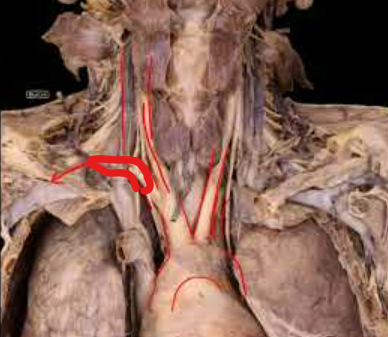

What is this structure and what does it anastamose with?

Left Circumflex Branch

RCA